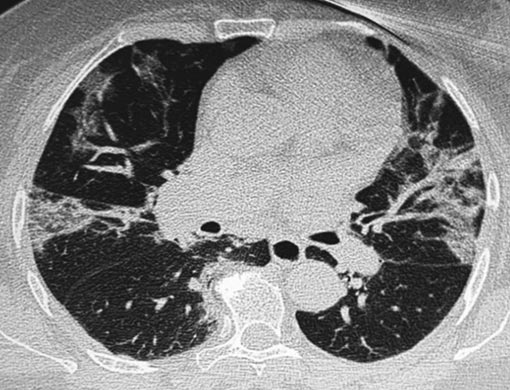

В течение следующей недели пациентка смогла полностью отказаться от дополнительной кислородной поддержки, свободно передвигалась в пределах палаты. Данные РКТ демонстрировали хорошую динамику в виде повышения прозрачности лёгочной ткани (рис. 3).

Рис. 3. Рентгеновская компьютерная томограмма к моменту завершения стационарного этапа лечения

Пациентка была выписана в удовлетворительном состоянии. Рекомендации на амбулаторный этап включали продолжение антикоагулянтной терапии ривароксабаном 10 мг 1 раз/сут, приём таблеток преднизолона по снижающей схеме до полной отмены, внутримышечные инъекции бовгиалуронидазы азоксимера по 3 млн ЕД 1 раз в 5 дней (общей продолжительностью до 15 инъекций). Назначена контрольная РКТ грудной клетки через 3 мес после выписки.